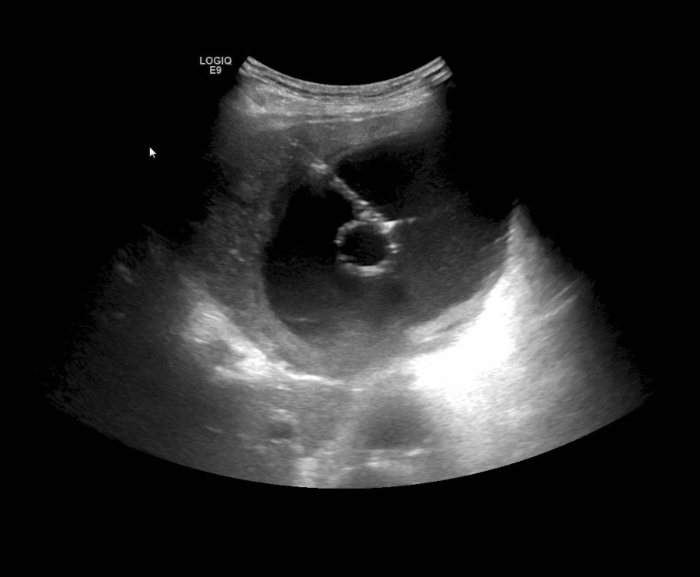

置入猪尾巴管引流出脓液

消化内科主任张排旗与超声科主任罗利红联合会诊,考虑患者发热和肝囊肿合并感染有关,决定给予抗感染治疗的同时,行超声引导下肝囊肿合并感染穿刺置管引流术。置管后,患者发热消退,腹痛缓解,脓腔明显变小,引流出500ml脓液,并进行细菌培养,结果为大肠埃希菌。患者症状明显缓解,感染得到控制,恢复良好。